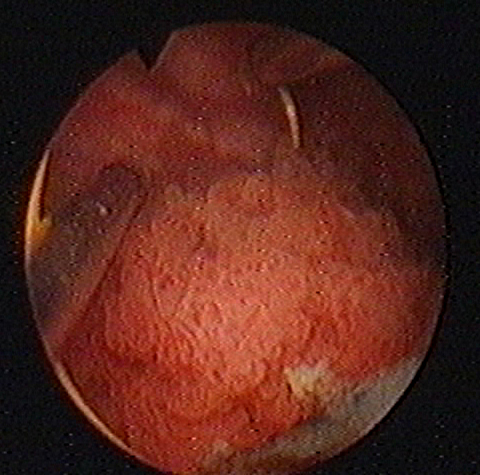

Investigatii endoscopice ale tumorilor vezicii

Investigatii endoscopice De la introducerea ei in practica si pana in prezent, cistoscopia a reprezentat si reprezinta examenul fundamental, obligatoriu si indispensabil pentru diagnosticul tumorilor vezicaCiteste tot ... 1016 cuvinte

Dimensiune mica

+ cu imagini |